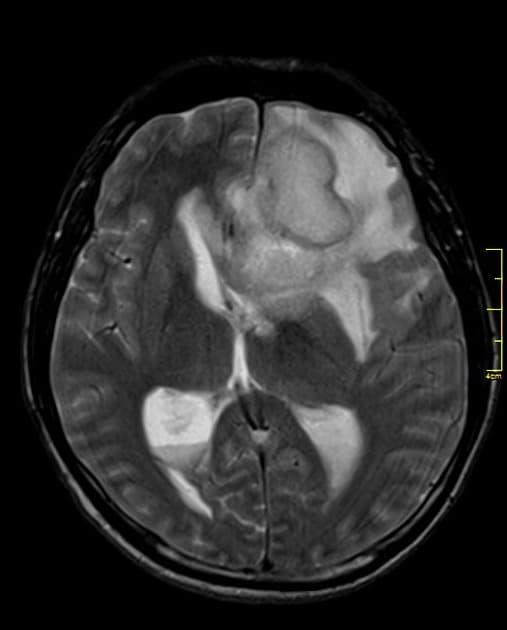

- Nhiều tổn thương bắt thuốc dạng viền (ring-enhancing) rải rác ở cả hai bán cầu đại não (cerebrum) và tiểu não (cerebellum), các tổn thương này có tín hiệu giảm trên hình ảnh T1 WI, tín hiệu trung gian trên FLAIR WI, tăng quang viền sau tiêm thuốc cản quang, không hạn chế khuếch tán (no diffusion restriction), xung quanh các tổn thương có phù vận mạch (vasogenic edema) bao quanh.

- Nhiều tổn thương bắt thuốc dạng viền (ring-enhancing) rải rác ở cả hai bán cầu đại não (cerebrum) và tiểu não (cerebellum), có tín hiệu trung gian trên FLAIR WI, tăng quang viền sau tiêm thuốc cản quang, không hạn chế khuếch tán (no diffusion restriction), được bao quanh bởi phù vận mạch (vasogenic edema).

Trường hợp này cho thấy nhiều tổn thương bắt thuốc dạng viền ở cả hai bán cầu đại não và tiểu não trên bệnh nhân có tiền sử ung thư phổi, rất gợi ý về di căn não. Các tổn thương di căn thường xuất hiện như những nốt tròn rõ ràng, tăng quang viền và kèm theo phù vận mạch lan rộng, mức độ phù thường nặng hơn so với kích thước tổn thương. Việc không có hạn chế khuếch tán giúp loại trừ áp xe não do vi khuẩn, trong khi tính chất đa ổ và phân bố rải rác làm tăng khả năng di căn hơn là u nguyên bào thần kinh đệm nguyên phát – thường là tổn thương đơn độc và nằm ở vùng đại não. Mặc dù u lympho có thể biểu hiện dạng tăng quang viền ở bệnh nhân suy giảm miễn dịch, nhưng thường gặp hơn là tăng quang đồng nhất và hạn chế khuếch tán. Chẩn đoán hình ảnh kết hợp với tiền sử bệnh lý đóng vai trò quan trọng trong việc thu hẹp chẩn đoán phân biệt. Chẩn đoán xác định thường cần sinh thiết, nhưng trong bối cảnh đã biết khối u nguyên phát, đặc điểm hình ảnh thường đủ để chẩn đoán.